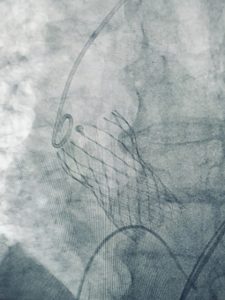

O Doutor Sérgio Diogo, médico hemodinamicista do Hospital São Francisco de Mogi Guaçu realizou em maio deste ano, um procedimento via femoral (pela virilha) sob anestesia local e sedação, para reverter um quadro de estenose aórtica, de uma paciente de 74 anos.

O tratamento é realizado com uma cirurgia para troca de válvula obstruída. “Hoje em dia é possível colocarmos um cateter de bioprótesis valvular aórtica, destinado para pacientes idosos com altos índices de risco cirúrgico para cirurgias convencionais, que chamamos de abertas” comenta o médico. A cirurgia é minimamente invasiva, levou cerca de duas horas e foi a primeira realizada com a técnica pela virilha.

Nos casos anteriores a prótese valvar foi implantada por minitoracotomia – uma pequena abertura no tórax do paciente – sob anestesia geral. Cerca de 30% dos pacientes com estenose aórtica tem idade avançada ou apresentam alto risco cirúrgico devido a doenças associadas, por isso não podem ser operados. A evolução tecnológica permitiu abordar esta fração de pacientes considerados inoperáveis, com raríssimos casos registrados de complicação vascular periférica ou necessidade de marcapasso definitivo.